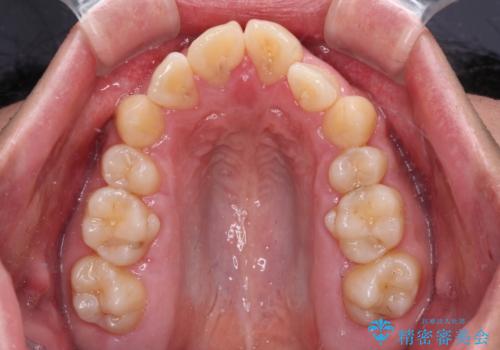

- 学生時代に抜歯矯正した歯列が後戻りしてきたとのことで来院された患者様です。

舌の突出癖が原因で上顎前歯が前方に移動したと考えられたため、舌のトレーニングを徹底して行っていただきながら、後戻りを解消していくこととしました。

上顎歯列全体がスムーズに後方移動でき、1年で治療を終えることができました。